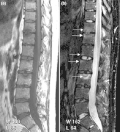

Imaging

-

T2-weighted MRI (sagittal) of index finger in PsA (mutilans form) showing probable erosion (increased signal) at base of the middle phalanx (long thin arrow), synovitis at the proximal interphalangeal joint (long thick arrow), soft tissue edema (short thick arrow), and diffuse bone edema (short thin arrows) of the proximal phalanx. -

T1 weighted axial MRIs of the fingers in PsA. (a) Pre- and (b) post-contrast showing dactylitis due to flexor tenosynovitis at the second finger with enhancement and thickening of the tendon sheath (large arrow), and synovitis at proximal interphalangeal joint (small arrow). -

T1-weighted semi-coronal MRI of sacroiliac joints (a) before and (b) after contrast showing active sacroiliitis (arrow). -

Coronal T1-weighted MRI of fingers in PsA. (a) Pre- and (b) post-contrast showing active synovitis at proximal and distal interphalangeal joints (large arrows), joint space narrowing, bone proliferation at proximal interphalangeal joint, erosions at distal interphalangeal joint (white circle), enthesitis medial to proximal interphalangeal joints. -

(a) STIR Sagittal MRI of ankle showing enthesitis at Achilles tendon insertion (thick arrow), synovitis of ankle joint (long thin arrow), and bone marrow edema at tendon insertion (short thin arrow). T1-weighted images, before (b) and after (c) contrast, show enthesitis (large arrow) and bone erosion at tendon insertion (short thin arrows).